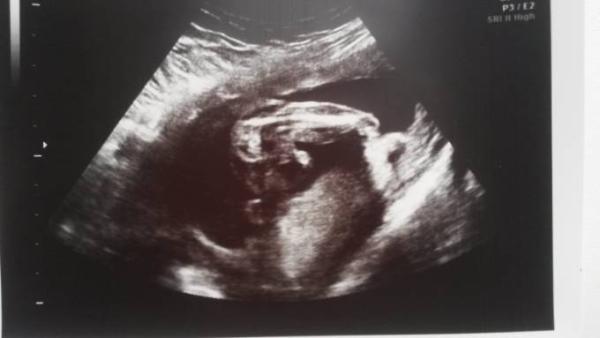

Hmm ich finde es bissle schwierig mich da fest zulegen. Ich häng dir mal mein Bild an. Bei uns wird es ein junge. Vielleicht hilft das..

Bild zu

Welche ssw war das? Soll das ganze Ding zwischen den Beinen der Penis sein oder der Hoden und nur das Pünktchen ganz vorne dran?

Das war 17 ssw Das zwischen den Beinen ist alles der Penis. Ist nah aufgenommen. LG